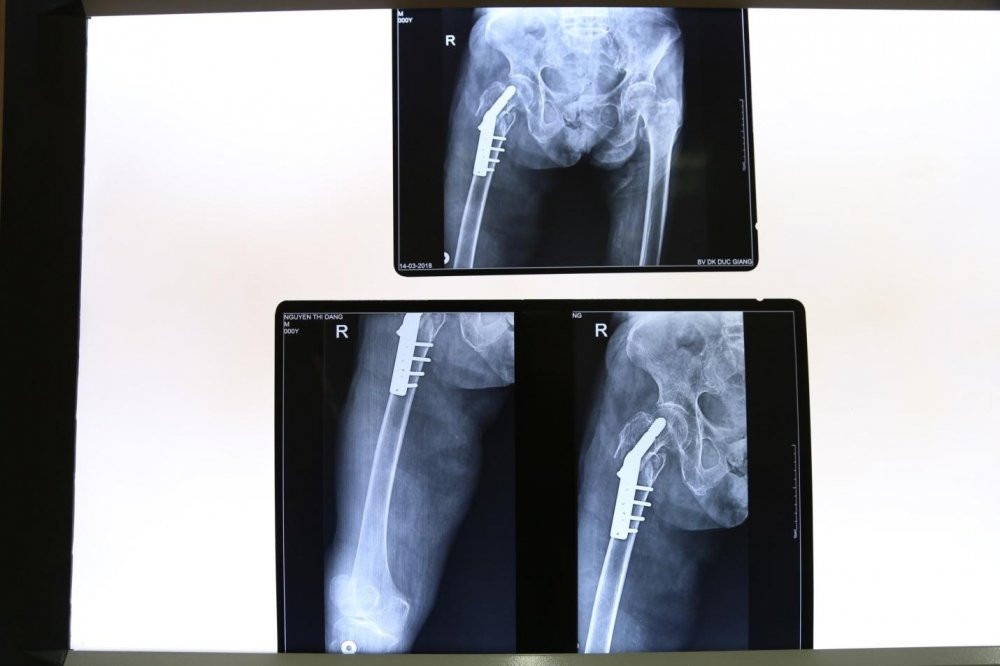

Sau khi chụp X-quang và làm các xét nghiệm, bệnh nhân được chẩn đoán gãy mấu chuyển xương đùi phải. Ngay sau đó, bệnh nhân được chỉ định phẫu thuật kết hợp xương dưới màn hình tăng sáng.

Hình ảnh sau ca phẫu thuật cho cụ bà 105 tuổi.